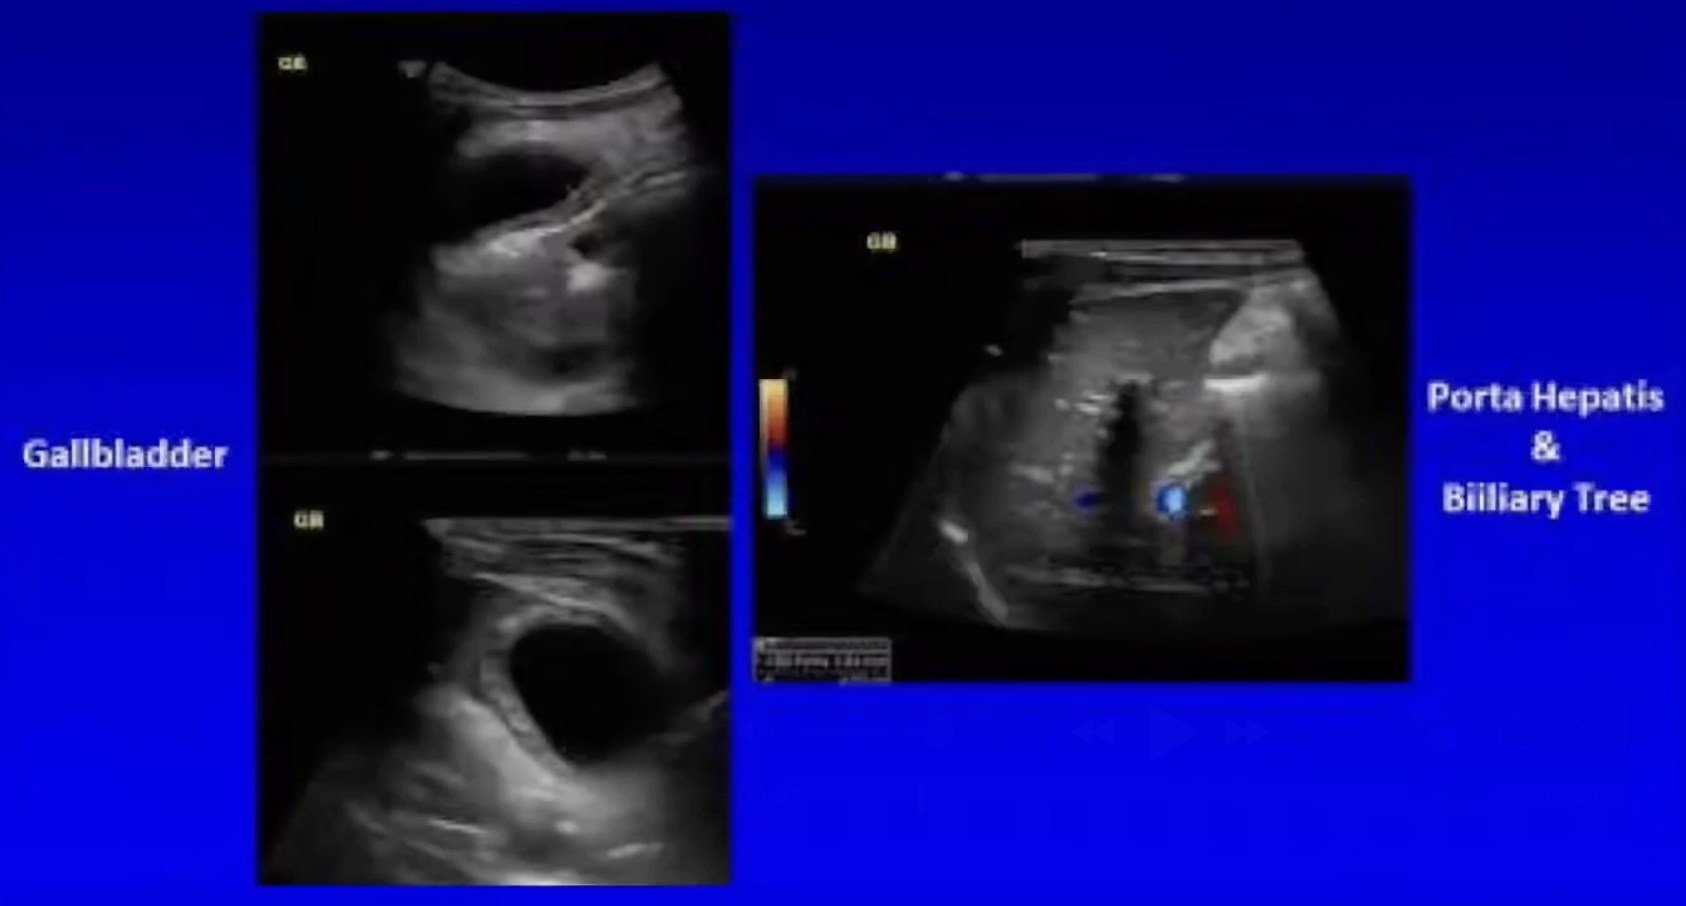

• US shows normal appendix, a very thickened gallbladder without stones, and a normal biliary tree.